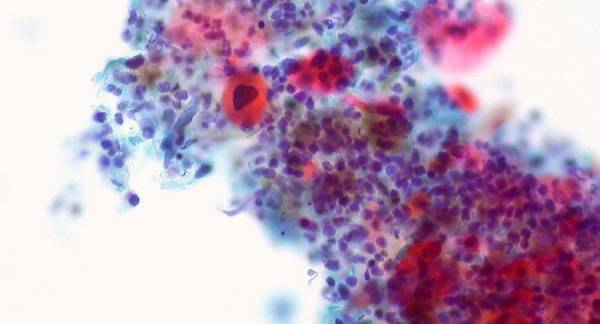

ảnh minh họa